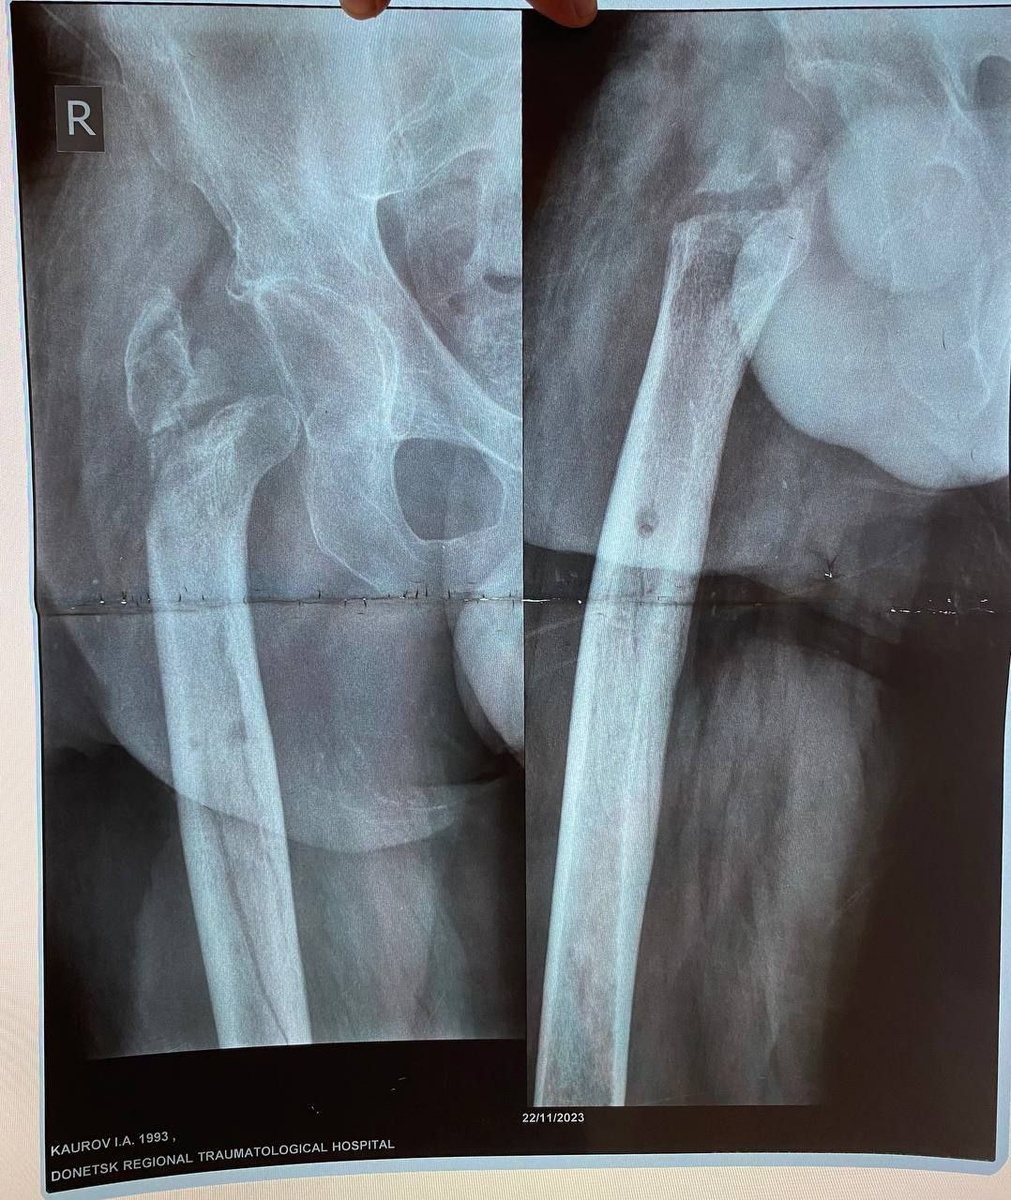

Недавно в Луганской республиканской клинической больнице провели уникальную операцию. Бойцу с тяжелейшим ранением бедра восстановили длину ноги и вернули возможность нормально ходить.

Врачи работали в рубцовой ткани после множества операций, убрали очаги инфекции и с помощью специальных конструкций буквально заново собрали сустав.